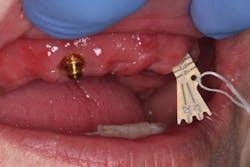

Technique for determining the need for a reline—maxilla:

Since a minimum of four implants are in place, it is very difficult to feel a "squish." Instead, I line the inside of the denture with light-body impression material, seat the denture on the abutments, and remove the denture after the material sets. Probe the impression material in multiple locations (figures 16–18). If probing is shallow and consistent through the denture, a reline is not indicated. If any areas are deeper, a reline is indicated. Note: The attachments are clearly visible in Figures 17 and 18, but often a thin layer of impression material will cover them.